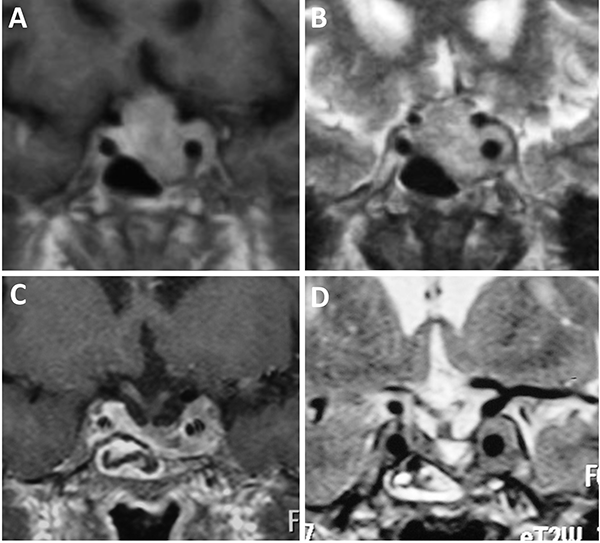

Clasificación de Knosp

En 1992 Knosp et al. publicó una clasificación para cuantificar la invasión del seno cavernoso (Tabla 3). Esta clasificación evalúa la extensión paraselar tomando como referencia la arteria carótida del lado a evaluar. Se elige un corte coronal de RM donde se visualiza la porción supracavernosa e intracavernosa, se traza una línea intercarotídea y se categoriza al paciente según el grado de invasión del adenoma del grado 0 al 4 (fig. 5).34

Figura 5: Adenomas hipofisarios Knosp grado 4. A-D: Obsérvese el englobamiento carotídeo.